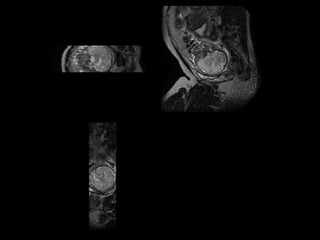

Retrospective motion correction

Orthogonal stacks of

misaligned 2D slices

Localising fetal organs can be used to initialise motion correction.